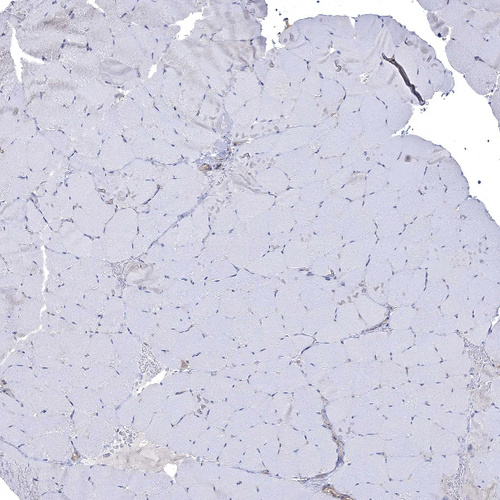

Immunohistochemistry analysis in human testis and skeletal muscle tissues using HPA040446 antibody. Corresponding SPAG9 RNA-seq data are presented for the same tissues.